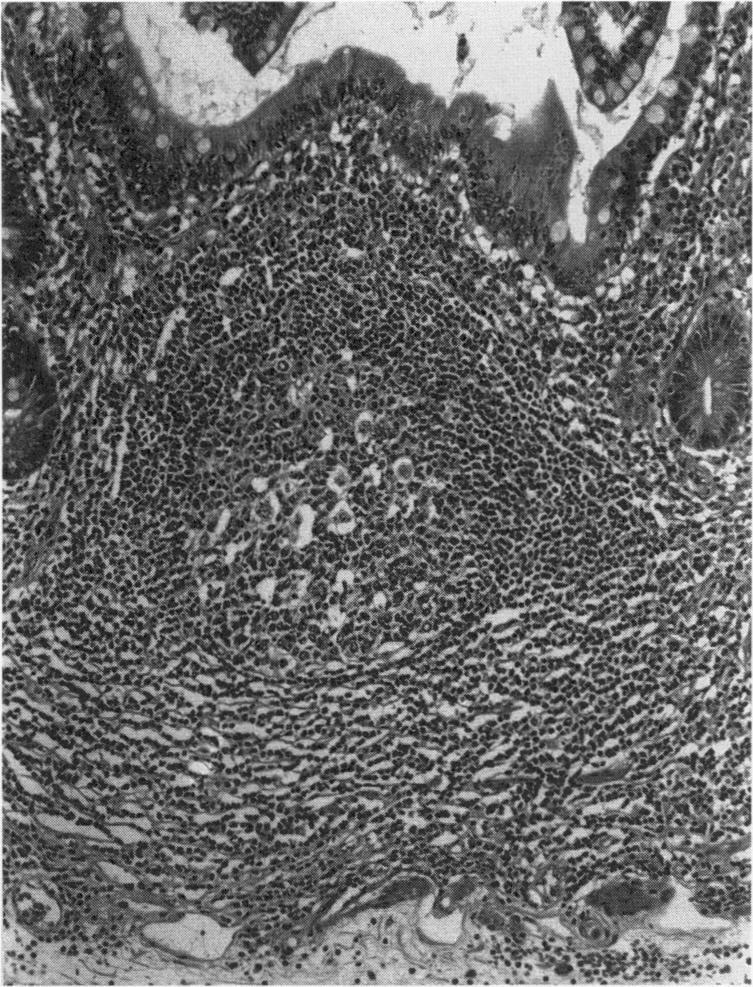

Primary gastric low-grade B-cell lymphomas are neoplastic mimics of mucosa associated lymphoid tissue (MALT) as exemplified by Peyer's patches in the terminal ileum. Architectural and immunophenotypic properties of the neoplastic cells suggest that they originate from MALT-derived marginal zone B-cells. Paradoxically, the normal human stomach is devoid of organized MALT within which a lymphoma can develop. Lymphoid tissue is acquired in the stomach in response to antigenic stimulation, predominantly associated with Helicobacter pylori infection. Studies of patients with low-grade MALT lymphoma have confirmed a high incidence of H. pylori infection and suggest that the infection predates neoplastic transformation. Certain morphological features of MALT lymphomas suggest that the tumor cells remain responsive to antigen drive. Given the close association between gastric MALT lymphoma and H. pylori, it is possible that this organism provides such a drive. In vitro studies have shown that the tumor cells proliferate in a T-cell-dependent way to the presence of H. pylori. Several studies have now demonstrated that eradication of the organism in patients with low-grade gastric MALT lymphoma can result in regression of the tumor. In cases with a high-grade component, the associated low-grade part may regress, but most high-grade gastric MALT lymphomas are unresponsive to this conservative therapy.

原发性胃低度B细胞淋巴瘤是黏膜相关淋巴组织(MALT)的肿瘤性模仿物,如回肠末端的派尔集合淋巴结所示。肿瘤细胞的结构和免疫表型特征表明它们起源于MALT来源的边缘区B细胞。矛盾的是,正常人类胃中没有可发生淋巴瘤的有组织的MALT。胃中的淋巴组织是在抗原刺激下获得的,主要与幽门螺杆菌感染有关。对低度MALT淋巴瘤患者的研究证实幽门螺杆菌感染的发生率很高,并表明感染先于肿瘤转化。MALT淋巴瘤的某些形态学特征表明肿瘤细胞仍然对抗原驱动有反应。鉴于胃MALT淋巴瘤与幽门螺杆菌之间的密切关联,这种生物体有可能提供这样的驱动。体外研究表明,肿瘤细胞在幽门螺杆菌存在的情况下以T细胞依赖的方式增殖。现在有几项研究表明,根除低度胃MALT淋巴瘤患者体内的这种生物体可导致肿瘤消退。在有高级别成分的病例中,相关的低级别部分可能会消退,但大多数高级别胃MALT淋巴瘤对这种保守治疗无反应。